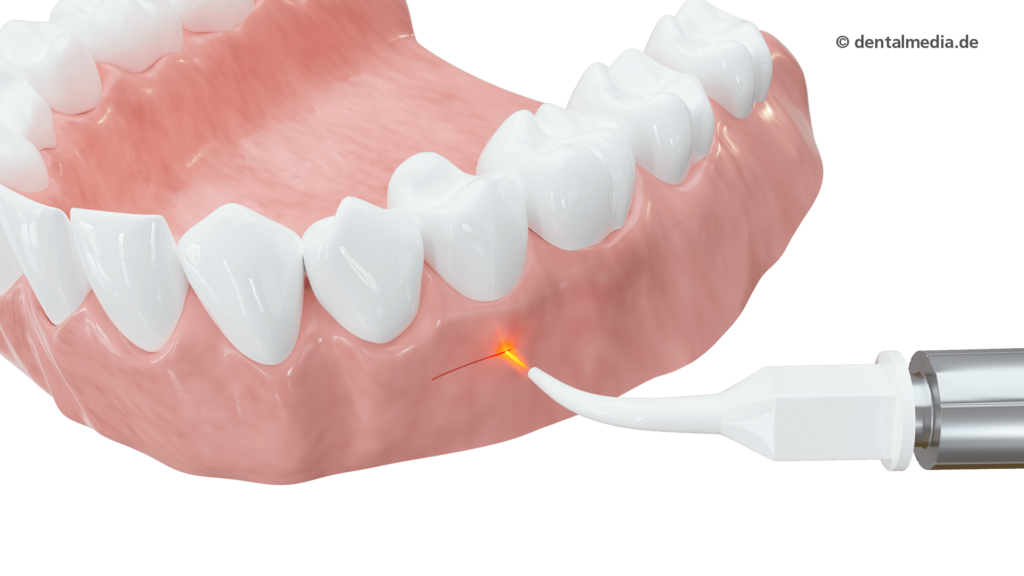

Schonend Lasern

Laser sind aus der modernen Medizin nicht mehr wegzudenken und finden auch in der Zahnmedizin immer größere Beachtung. Zahn- und Zahnfleisch-Behandlungen, die mit einem Laser unterstützt werden, sind äußerst schonend, sicherer und somit angenehmer für den Patienten.

Der Laser eignet sich für verschiedene Anwendungsgebiete. Speziell bei der Wurzelkanalbehandlung hat sich der Einsatz von Laserlicht bewährt. Dank der Tiefenwirkung können die Bakterien effektiv abgetötet werden. Aber auch bei empfindlichen Zahnhälsen, zur Behandlung von Herpes oder in der Chirurgie bietet das Gerät viele Vorteile. Der Eingriff erfolgt in der Regel sanfter und die Patienten haben deutlich weniger Schmerzen, wodurch sich ein schneller und besserer Heilungsverlauf ergibt.

Chirurgie

Wenn das Zahnfleisch operativ behandelt werden muss, bietet der Laser gegenüber dem Skalpell eine ganze Reihe von Vorteilen: Die Behandlung verläuft blutungsarm oder sogar komplett blutungsfrei. Wir erreichen eine schnellere Wundheilung und deutlich weniger Schmerzen. Eine Infektion der Wunde ist nahezu ausgeschlossen und häufig kann auf Antibiotika verzichtet werden.